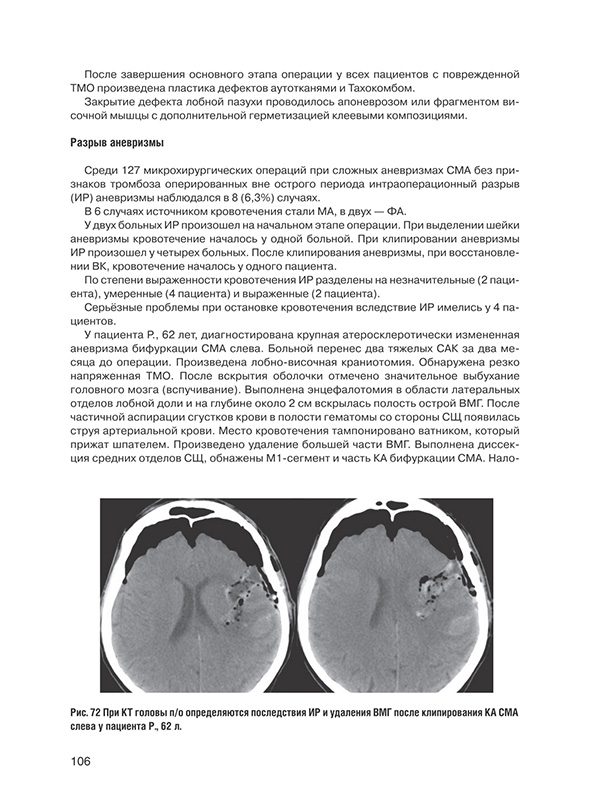

Разрыв аневризмы